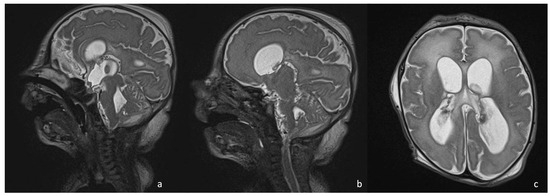

5.4. Effusions and Empyema

5.3. Ventriculomegaly and Hydrocephalus